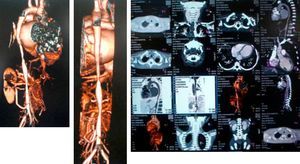

A computed tomography scan revealed hypoplasia of the right vertebral artery (V4), left subclavian stenosis and narrowing of the descending aorta with arteritis data on the wall, yuxtadiafragmática and transverse diameters of 4.5–5.0mm. Were also stenosis in the origin of the superior mesenteric artery (3.3mm) and significant stenosis in the origin of the right renal artery (Fig. 1).

The diagnosis of TA III was based on the following: decreased peripheral arterial pulses and limb claudication, pressure difference greater than 10mmHg, murmur over the aorta, arterial hypertension and angiographic abnormalities (thoracic ascending and abdominal aorta and renal arteries).